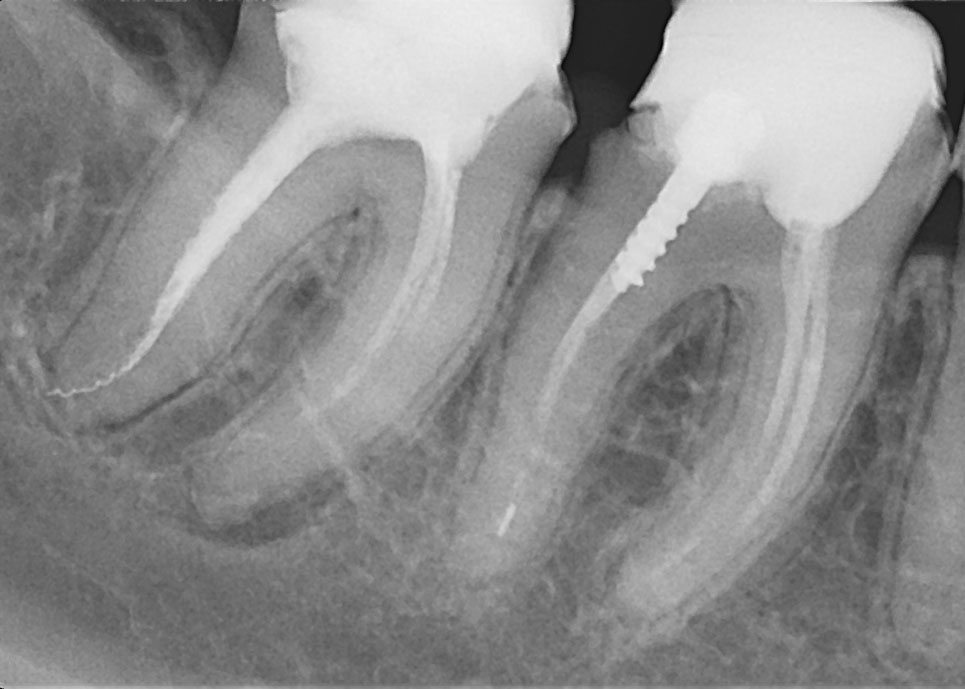

В настоящее время доступны следующие возможности для диагностики:

- Ретроальвеолярная рентгенография;